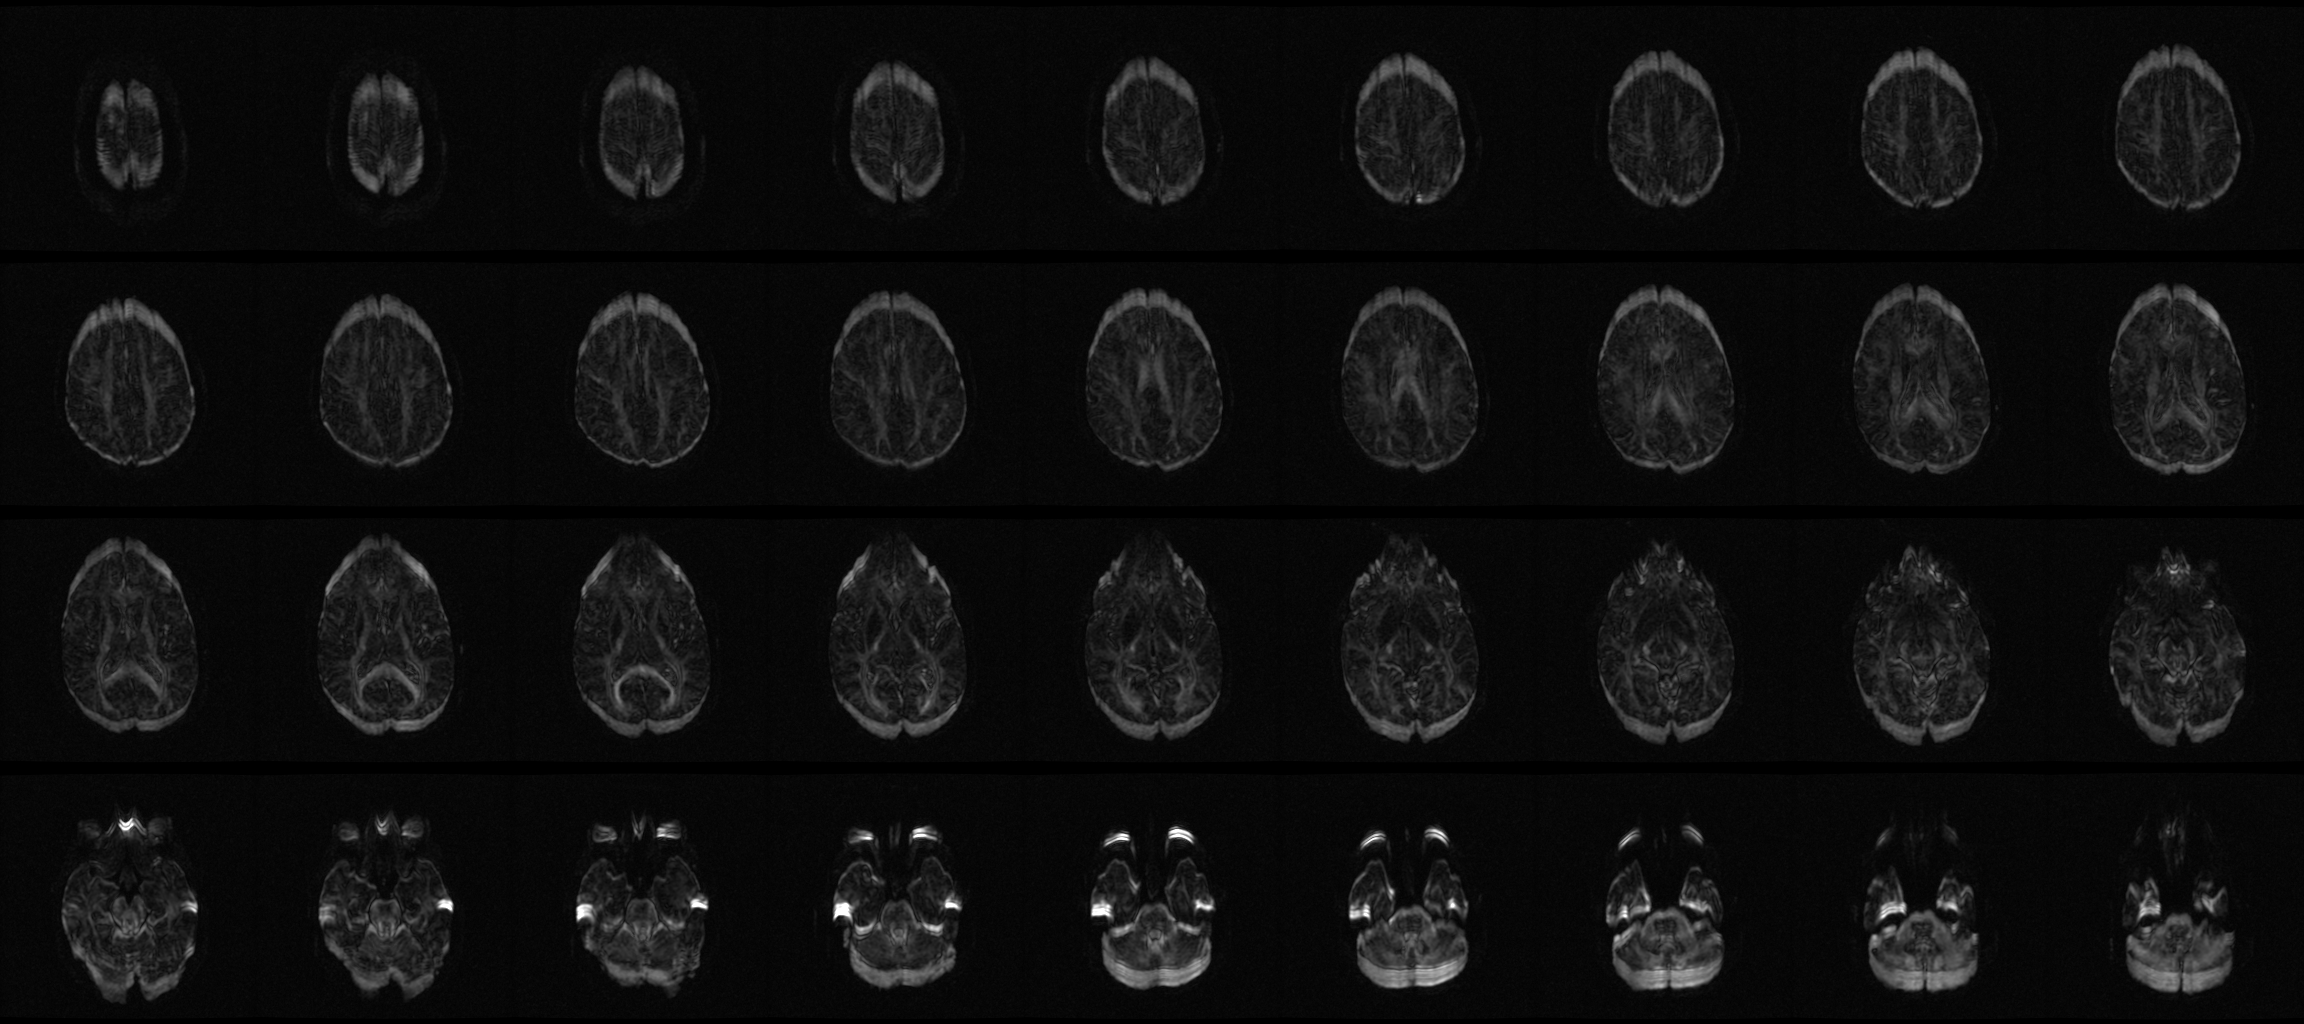

This slices along axis 2 (the IS image coordinate) at index 20, crops out the non-DWI baseline images, tiles the 12 DWIs into a 4-by-3 array, quantizes to 8 bits, and save out to a PNG image:

This allows one to verify that axis ordering is right- if the "sizes" field was wrong you would not see coherent images, or they would not show the same anatomical slice shown here.